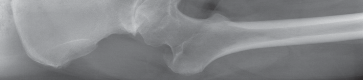

Thorough preoperative evaluation is mandatory. Plain radiographs remain the cornerstone of preoperative planning. An anteroposterior (AP) pelvis radiograph, along with AP and lateral radiographs of the affected hip, are highly recommended. These images allow for the assessment of bone quality, joint space narrowing, osteophyte formation, and the presence of subchondral cysts.

Surgeons must strictly template the radiographs to determine optimal component size and precise component position. The primary goals of templating are the restoration of the anatomic center of rotation, the reproduction of native leg length, and the re-establishment of femoral offset. Failure to restore offset can lead to abductor laxity, increasing the risk of instability and gait abnormalities. Occasionally, advanced imaging such as a computed tomography (CT) scan or magnetic resonance imaging (MRI) is indicated. These modalities are particularly useful to assess severe acetabular bone loss, large subchondral cysts, and complex three-dimensional deformity in developmental dysplasia during primary or revision total hip replacement.